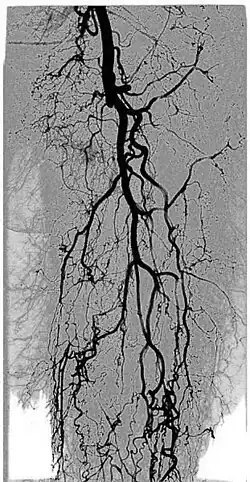

Digital variance angiography (DVA)

See also: Digital variance angiography

The diagnostic value of radiographic images is limited by image quality, which can be measured through signal-to-noise ratio (SNR) calculations. The higher the value of SNR, the better the image. The SNR can be increased initially by enhancing the "signal" or "contrast", which is the intensity difference between the object of interest and the background. This is usually done by adding contrast medium to increase the attenuation values of the object, while holding the background values constant.[1][2][3][4]

By allowing visualization of movements, kinetic imaging offers a new type of motion-based contrast. In many cases, the kinetic image will have a higher SNR (better image quality) compared to traditional images for moving objects.[2][6][1][3][4]

This improvement in SNR and image quality has been studied by Gyánó M. et al. (2018)[3] and Óriás V. et al.(2019)[4] in the field of traditional angiographic imaging and carbon-dioxide imaging. Their findings indicate that by using the kinetic imaging (or as they called this method in the case of angiographies, digital variance angiograpy, DVA) for processing angiographic image sequences, the quality improvement may increase diagnostic insight and it also creates a quality reserve, which means that DVA could provide the same level of image quality, as the gold-standard DSA technique, but the dose of administered radiation and/or contrast agent could be lowered.[3]

The kinetic image may allow visualisation of physiological movements, such as pulsing of the aorta, passing of a contrast agent bolus in the arteries, movement of the thoracic diaphragm, inflation and deflation of the alveoli in the lungs, or the constantly moving gastrointestinal tract.